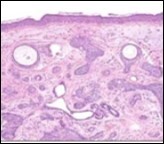

Lesions are generally superficial and infrequently invade lower dermis. Tendency for peri-neural or intra-neural infiltration, cogitated in adjunctive cutaneous carcinomas, is exceptional in desmoplastic trichoepithelioma. Nevertheless, desmoplastic trichoepithelioma can be exemplified as a component of particularly desmoplastic, cutaneous carcinomas demonstrating foci of peri-neural involvement 4, 5. Figure 1, Figure 2, Figure 3, Figure 4, Figure 5, Figure 6, Figure 7, Figure 8.

Figure 3.Desmoplastic trichoepithelioma exhibiting accumulated basaloid epithelial cells disseminated amongst a background of abundant fibrous tissue stroma and an attenuated superimposed epidermis 10.